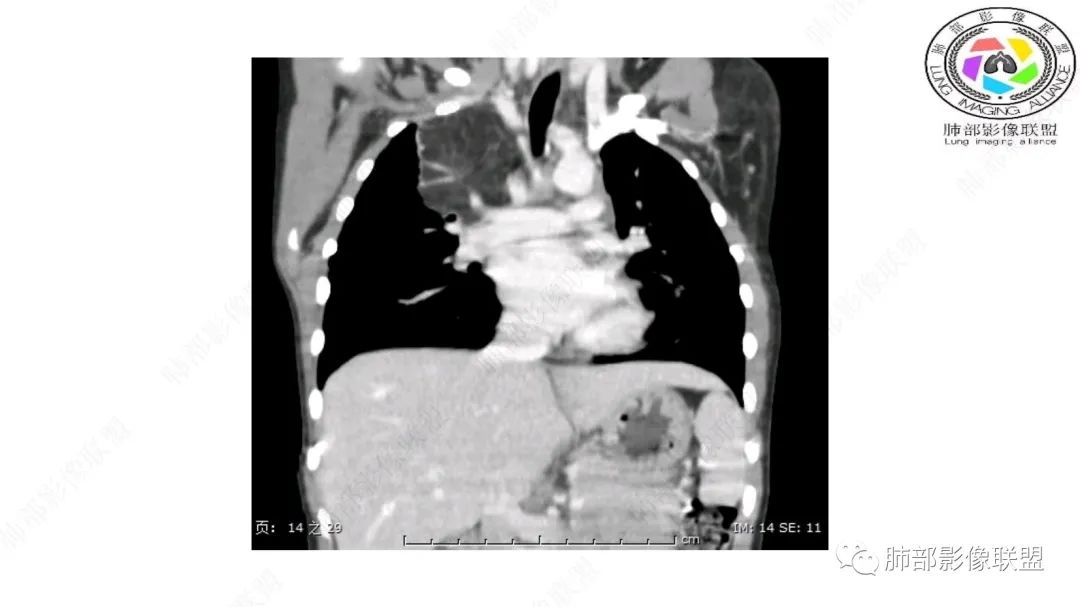

右上纵隔混杂密度肿块,边缘光整,与纵隔分界清,其内多发脂肪密度,增强无明显强化,其内血管穿行,考虑纵隔脂肪母细胞瘤,鉴别畸胎瘤,脂肪肉瘤。

右纵隔团状,密度不均,脂肪密度为主,内可见腺体样组织,类似乳腺,病灶边缘有分叶,与胸腺关系密切,增强后血管穿行。考虑胸腺脂肪瘤(不典型垂乳征),鉴别畸胎瘤。

3岁儿童,右纵隔占位,内部间多发脂质成分及斑片状稍高密度影,考虑纤维成分,增强似有强化。病灶内血管未见明显侵犯,可考虑脂肪母细胞瘤,冬眠瘤等。

三岁小儿,右侧纵隔巨大脂肪密度肿块,肺动脉穿行其中,密度欠均匀,未见明确实性成分,纵隔脂肪母细胞瘤,冬眠瘤鉴别纵隔脂肪增多症(多弥漫对称)。

患儿3岁 咳嗽检查发现纵隔占位。右肺上叶受压表现,占位以脂肪组织密度为主,似见分隔,首先考虑为脂肪母细胞瘤,鉴别脂肪瘤,畸胎瘤。

幼儿,右上纵隔团块状脂肪密度影,边缘清晰,内可见血管及支气管穿行,考虑脂肪瘤,鉴别畸胎瘤。

幼儿,右上纵膈团块,脂肪密度,内见分隔,增强病灶内见血管穿行,结合患者年龄,考虑脂肪母细胞瘤,鉴别脂肪瘤。

纵隔畸胎瘤,右前上纵隔团状脂肪密度?粘液样密度为主病变,病灶软边缘有分叶,内可见分隔,增强后血管穿行。3岁。考虑纵隔脂肪母细胞瘤,鉴别畸胎瘤。

定位肺外纵隔内,脂肪密度,内可见纤维分割,3岁,脂肪母,鉴别畸胎瘤。

右上纵膈混杂密度肿块,边缘光整,与纵膈分界清,其内多发脂肪密度,增强无明显强化,其内血管穿行,考虑纵膈脂肪母细胞瘤,鉴别畸胎瘤,脂肪肉瘤。

定位:肺内?尖段气管未见明显显示,腔静脉受压向右推移?病灶内可见前段动脉穿行,脂肪密度为主。

肿块起源于右上气管分叉处?强化动脉血管最后汇入右肺动脉上干。

右侧纵隔奇静脉水平起源?压迫上肺,包绕动脉?

小儿,右上纵隔占位,脂肪密度,血管未见破坏,考虑胸腺脂肪瘤,畸胎瘤。

右肺门上方,位于纵隔胸膜旁见巨大肿块,脂肪为主混合密度,内见细小血管影,肿块最大长径与纵隔胸膜平行,包绕右肺上叶肺动脉,右肺上叶及纵隔结构推压,无侵蚀破坏,良性肿瘤,起源纵隔胸膜血管平滑脂脂肪瘤。

跨肺门,包绕肺血管分支,邻近肺组织受压肺不张。

可以看到造影剂进入的丛状结构

密度不均,非纯脂肪成分。斑片状密度略高区域有轻度填充式强化。

婴幼儿,病变较大,跨肺门,分叶,富含纤维或黏液、含成熟脂肪,破坏力弱或无,浸润性生长模式不明显,未见远处转移。

综合:富含成熟脂肪的、可以有丛状结构的,可以有纤维或黏液的良性或低度恶性肿瘤。常见疾病谱:脂肪瘤、神经纤维瘤样错构瘤、冬眠瘤、血管脂肪瘤、髓脂肪瘤、脂肪母细胞瘤、黏液样脂肪肉瘤。

鉴别要点:病变成分不单一,非包绕神经结构、间质血管不显著、婴幼儿,良性或低度恶性。

第一个问题:定位:肺内?纵隔?

病灶属于交界区,主体位于肺内,占位效应明显,前方突入胸壁,胸腺受压变形,胸膜显示欠清楚;病灶包绕上叶肺动脉;似乎有体动脉供血。符合肺内的点:包绕上叶肺动脉分支;符合纵隔的点:前方似乎突入胸壁,与胸腺关系比较密切,但是与上腔静脉的关系提示病灶不支持纵隔来源,前纵隔的常规会将上腔静脉受压后移、外移,这是不符合的。

从这个角度符合肺内的,有一点不太踏实的是:似乎突入前胸壁。

手术记录:见右肺上叶肿物,肿物与右肺上叶关系密切。与纵隔无粘连,逐步分离肿物,见肿物大小约6cm*5cm,边界清楚,于右肺上叶粘连,边界清楚,肿物包绕右肺上叶血管及支气管。超声刀逐步游离肿物,完整切除肿物,右肺上叶肺组织无破溃,表面无出血。

1.右上肺-纵隔交界区巨块影,主体位于右肺一侧,紧贴胸腺、头臂干、右锁骨下动脉、上腔静脉、奇静脉等,不能分离,但病灶整体边界清楚。注意上述相邻腔静脉等结构未见受压变形,纵隔亦未见明显向左推移,至少提示两点:

2.肺动脉穿行也许是肺内来源最重要支持点!

CT扫描对脂肪类肿瘤常有独到价值。肿块孤立、边界清楚,未见周围浸润,较均匀脂肪样低密度,高度提示为良性!

发生于成人为脂肪瘤表现,婴幼儿自然会想到脂肪母细胞瘤。两者生物学行为并无本质区别。

脂肪母细胞瘤由成熟程度不同的脂肪组织、纤维间隔、黏液基质、小血管丛等间质成分组成,以脂肪组织与黏液样基质为主,其影像学表现取决于上述组织成分。典型的CT和MRI表现为:前后纵隔均可发生,常见于前纵隔;肿块大小不一,直径多在3cm~7cm,密度均匀,CT值呈水样或脂肪密度,脂肪组织密度或信号为主的肿块,其内密度或信号不均匀,可见粗细不一的分隔影,且有结节、片状影,后者可呈轻中度强化;结节状肿瘤包膜完整;弥漫性者包膜不明显,常呈浸润性生长;周围结构为受压和推移改变,可有少量胸腔积液,淋巴结无增大。